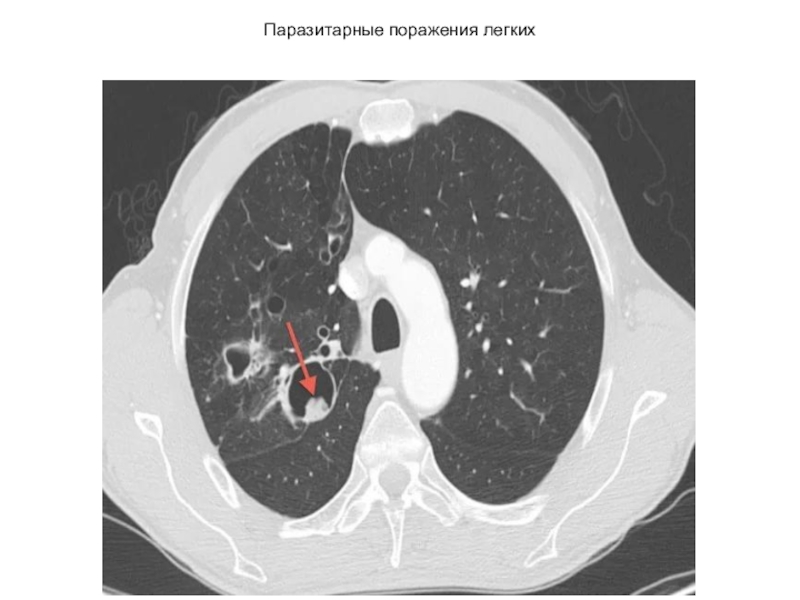

Слайд 63Паразитарные поражения легких

Паразитарные поражения легких